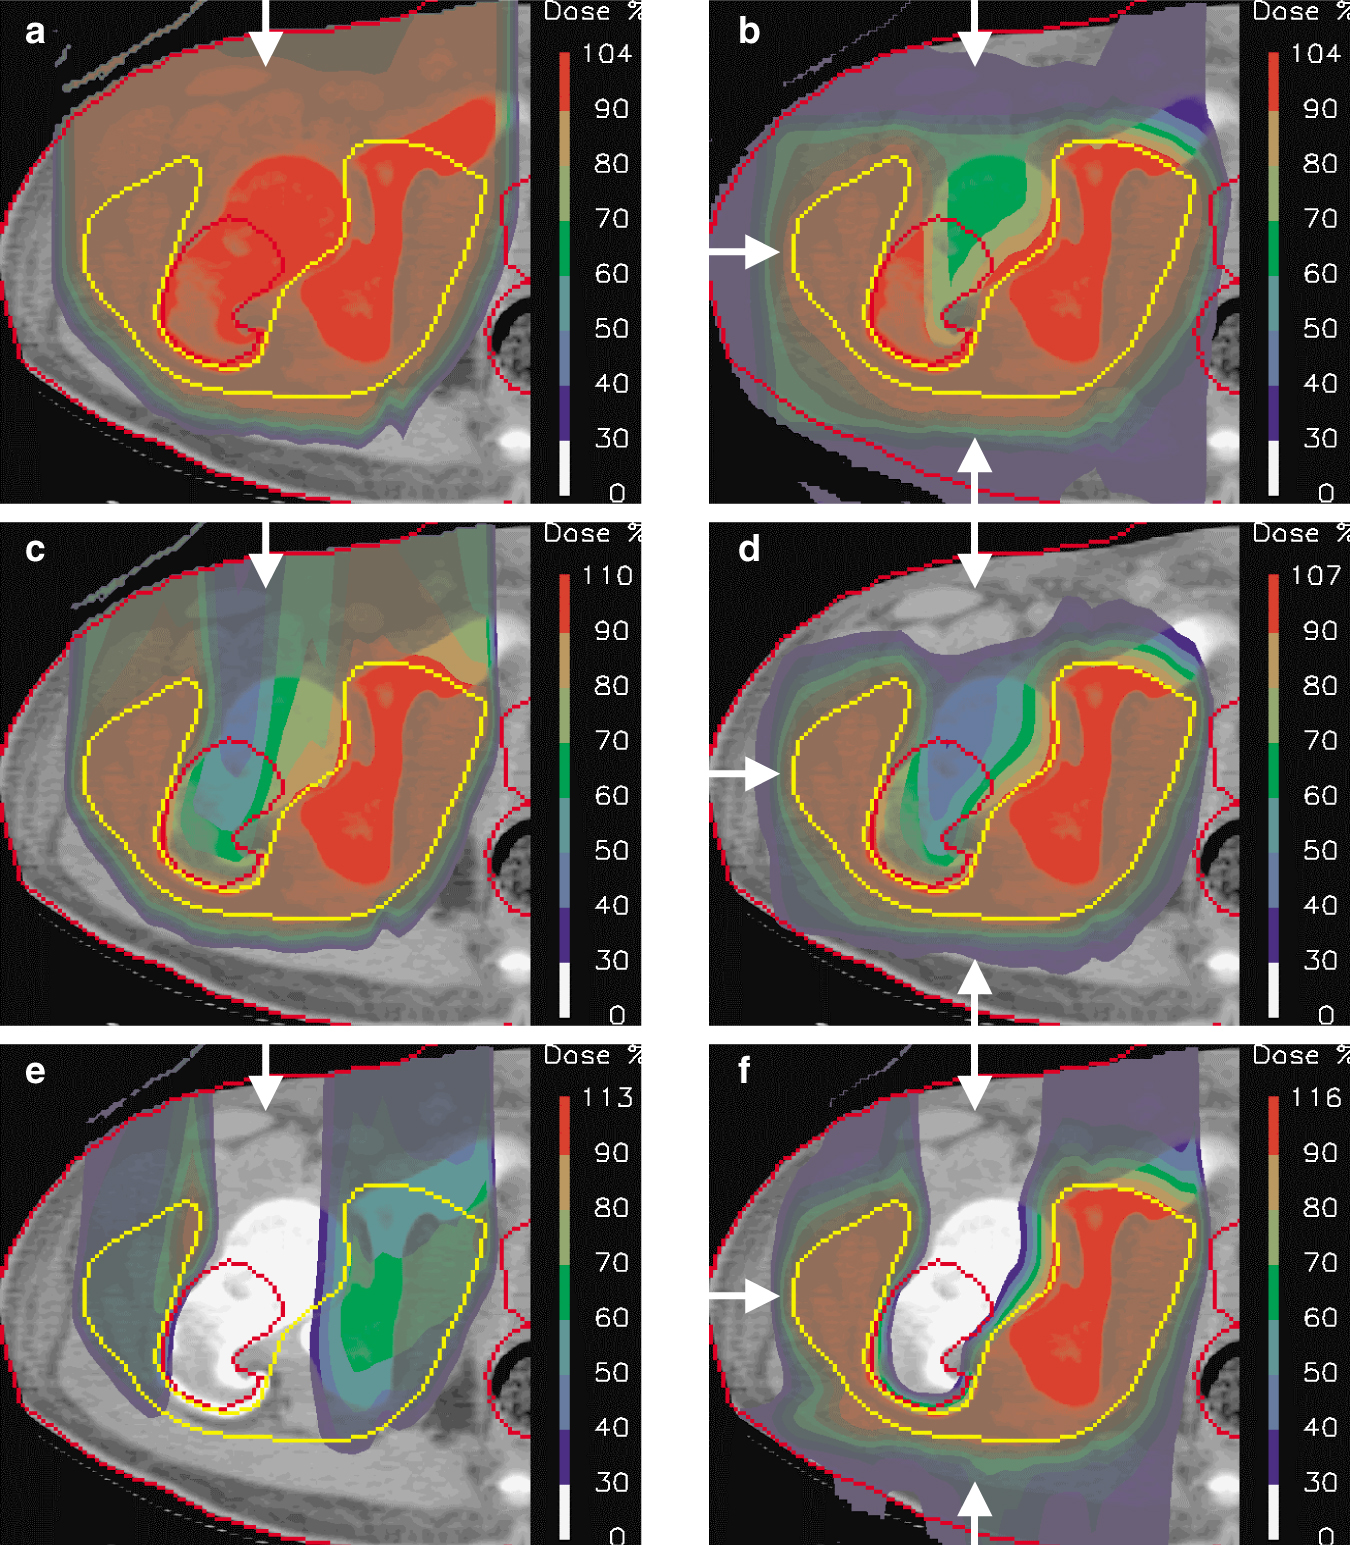

Calculated Dose distributions for irradiating a form of bone cancer called Ewing’s sarcoma. Each panel shows a single transverse section through the center of the tumor. The dose distribution is represented as semi-transparent color-wash (using the scale depicted at right, in which 100% indicates the desired dose to the tumor) overlaid on a CT section of the affected area. The target volume is delineated in yellow, and critical structures are outlined in red. Arrows indicate the incident field directions. (a) A single passively scattered proton beam (field). (b) A three-field approach in which all the fields are passively scattered. (c) A single-field approach using active beam scanning. (d) A three-field approach in which all fields use active beam scanning, but each field delivers a near-uniform dose to the target volume. (e) One of three fields used in the intensity modulated proton plan shown in panel f. This field alone delivers a highly nonuniform dose across the target volume. (f) A three-field, optimized intensity modulated proton treatment in which the individual fields deliver a highly nonuniform dose across the target volume. The result is a near-uniform, highly conformal dose to the target. Note, also, the high degree of sparing of the bone in the center of the high-dose region.

In practice, multiple, angularly separated fields are used to enhance the dose conformation to the target volume (figure

For a single field direction, passive scattering can provide excellent conformation of dose to the distal end of the target and good conformation laterally (figure 4(a)). However, because of the fixed depth-modulation of Bragg peaks across the whole field, passive scattering provides little conformation of dose to the proximal side of the target volume.

Passive scattering uses a single order of modulation. That is, its delivery is based on the successive modulation of range-shifted Bragg peaks along each delivered beamlet. This one-dimensional modulation is why the passive scattered field shown in figure 4(a) cannot provide conformation to the proximal side of target: It does not have enough degrees of freedom.

A natural progression from passive scattering is to increase the level of modulation inside a single field. One tactic is to modulate not only the weights of Bragg peaks as a function of depth, but also the relative fluence of individual beamlets across the plane of the delivered field. Such a third-order modulation is the idea behind active beam scanning, in which each field is made up of many (typically thousands) of pencil beams whose energies and lateral positions are chosen so as to locate their Bragg peaks within the target wherever they are needed and whose weights can be individually adjusted. In general, any physically possible dose distribution can be realized by using gradient-based optimization algorithms to determine the appropriate weights. For instance, one may elect to have each field deliver a uniform dose to the target volume while ensuring, in contrast to passive scattering, that the high-dose area of the combined fields conforms also to the proximal surface of the target volume. Figure

Spot-scanning can be used to deliver any desired (and physically possible) dose distribution. In particular, it can deliver intensity-modulated proton therapy (IMPT), just as in intensity modulated x-ray therapy. In IMPT, a uniform dose within the target can be constructed from a number of individually nonuniform proton fields. Strictly, IMPT does not provide an additional degree of freedom, but it does allow the full exploitation of all the degrees of freedom provided by the many thousands of individually weighted and three-dimensionally distributed Bragg peaks. Figure